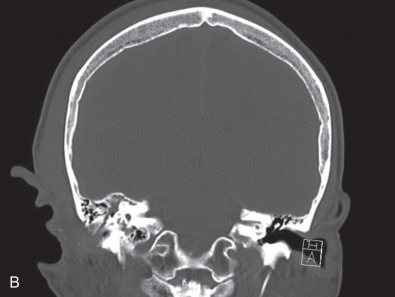

Computed tomography (CT) is the best modality for assessing temporal bone fractures ( Fig. 1.17.2 ). Opacification of air cells and pneumocephalus can suggest a fracture. Pneumolabyrinth suggests OC involvement and is found in up to 8% of fractures. A head, maxillofacial, or cervical CT can detect a fracture without the need for a dedicated temporal bone scan. The sensitivity and specificity of a maxillofacial CT scan in cases of blunt head trauma and associated vascular injury are greater than 90% and imply a negative predictive value of >95%. A separate HRCT can add cost, radiation exposure, and time to a work-up without significantly changing management. However, if standard imaging does not show a fracture but physical exam suggests its presence, or if management dictates the superior anatomical information offered by HRCT, then a dedicated temporal bone CT should be obtained. In cases where surgical management is considered or an unreliable clinical exam is present, a HRCT scan provides adjuvant information that changes treatment.

HRCT should include proper filters for bone edge detection and reconstructions from small fields of view with minimal slice thickness (e.g. 0.5 mm) and spacing (ideally 0 mm). Scans obtained with spiral technique or from multidetector scanners using 0.5 mm 3 or smaller voxels allow for reconstructions in any plane without loss of resolution. For pediatric patients, low-dose radiation protocols may be used; however, evaluation of small structures may be difficult. The evolution of flat panel CT is a promising development that may offer even higher resolution of bony anatomic detail with lower total radiation dose. No matter the technique used for HRCT, the clinician should review the images and correlate physical findings with imaging ( Box 1.17.1 ).